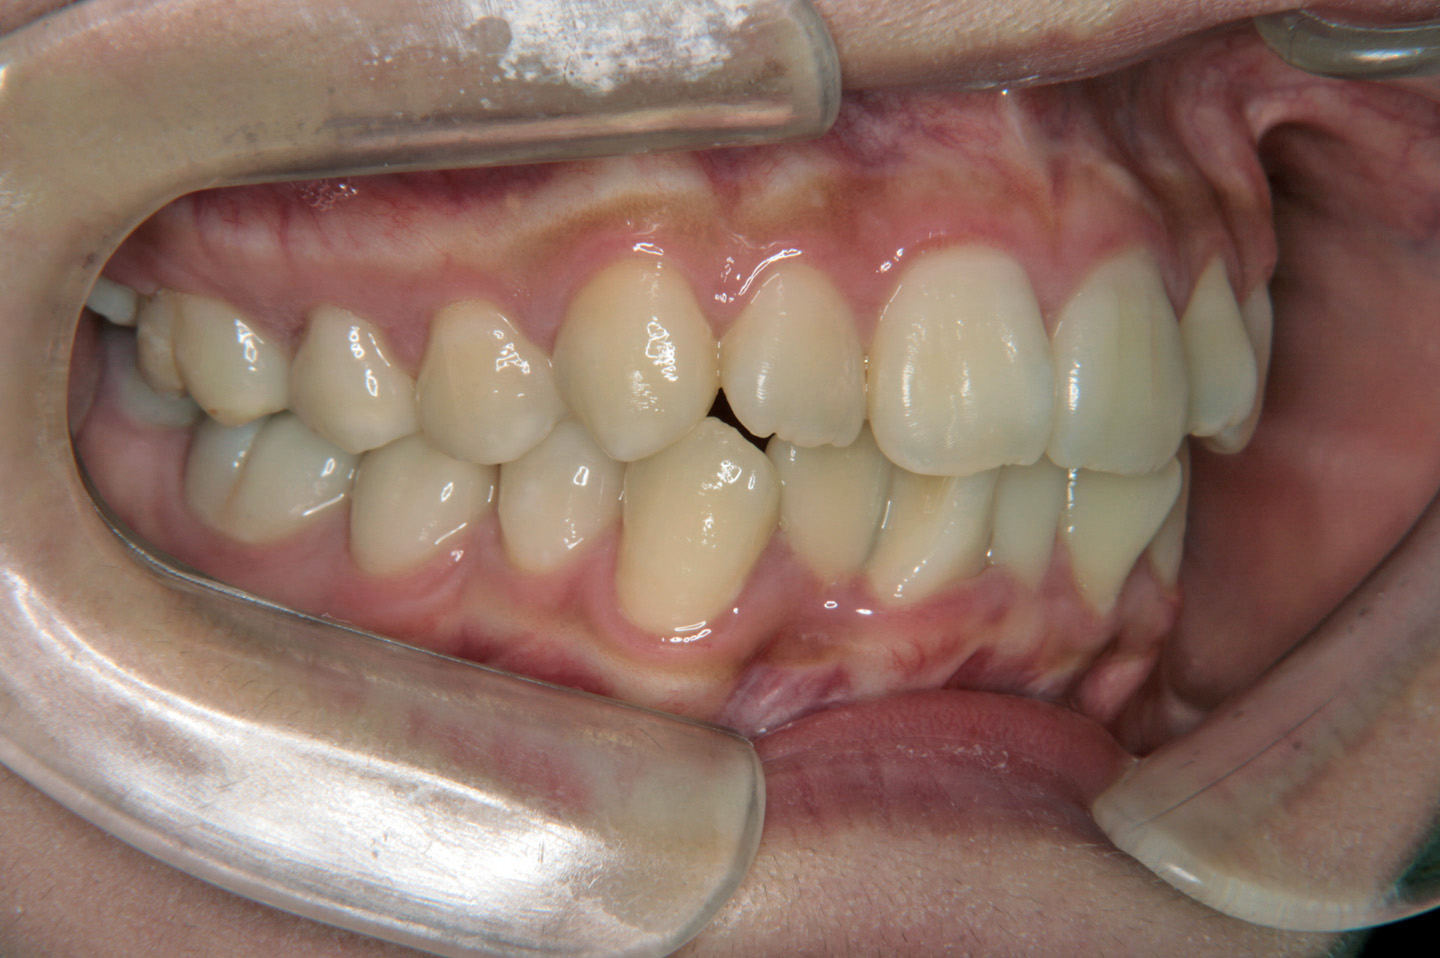

下の前歯のデコボコを気にされて来院された成人の女性です。プロファイルは良好でしたが下顎前歯の叢生が著しかったため下の前歯1本抜歯させていただき上顎は裏側からの装置(リンガルブラケット)で歯並びを整えました。ボンデッドワイヤーとリテーナーを併用した保定に移行しております。

初診時

動的治療終了時